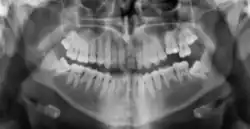

Radiographic appearance

On radiographs, enamel appears as the most radiopaque (white) structure due to its high mineral content.[19] Dentine and cementum are less radiopaque and are usually indistinguishable from each other.[19] The pulp chamber and root canals are radiolucent (dark), centrally located within the tooth structure. The periodontal ligament appears as a thin, radiolucent line between the root and the lamina dura.[19]

Figure 6: X-ray showing permanent dentition[20]